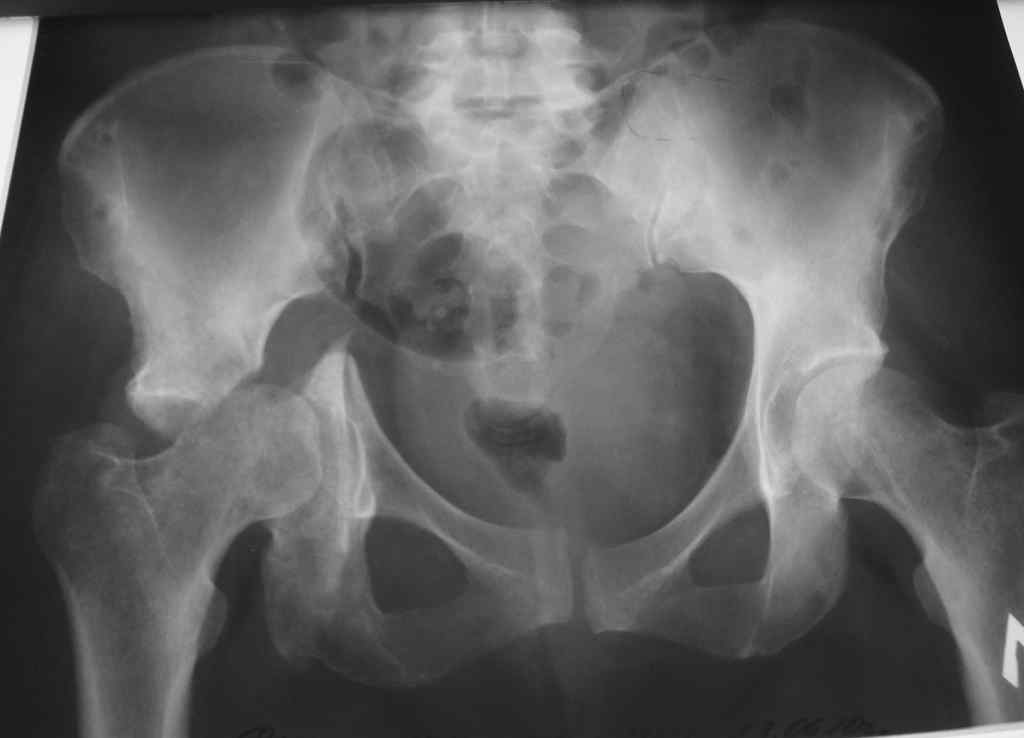

Доброе время суток уважаемые коллеги. На обсуждение выносится пациентка 42 лет. Травма 7

месяцев назад - ДТП. В одной из районных больниц выполнена фиксация таза и бедра в аппарате.

Через 4 мес. аппарат демонтирован. На контрольных рентгенограммах через 3 недели после

демонтажа аппарата выяснилась данная рентгенкартина и пациентка направлена к нам в клинику

с диагнозом ложный сустав дна вертлужной впадины.